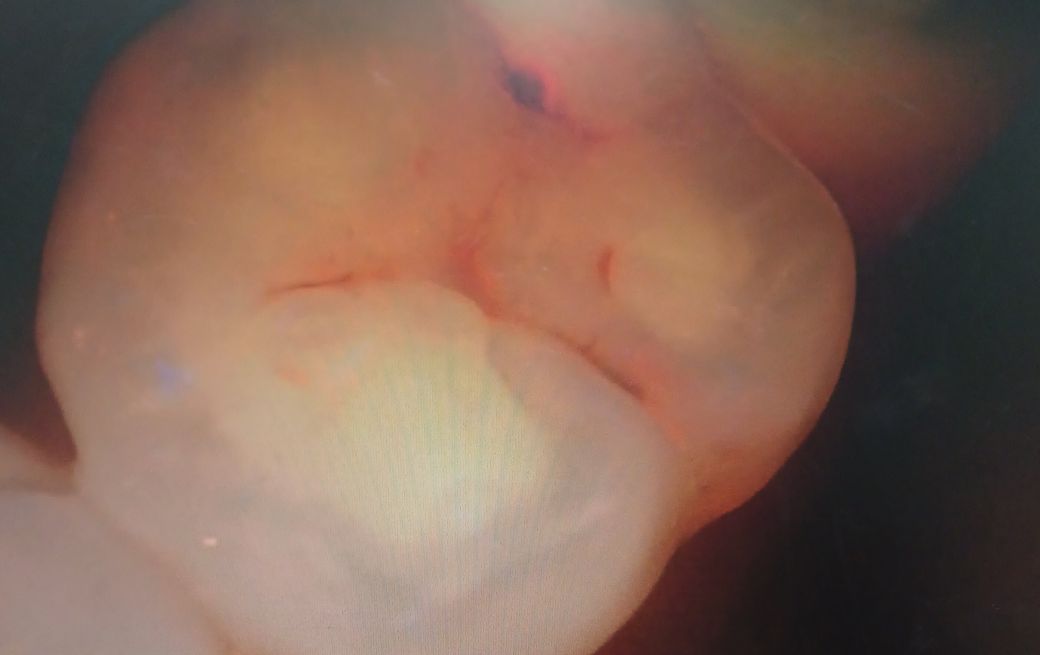

큐레이 사진으로 보았을 때 해당 치아는 치료를 하는 것이 맞습니다. 특히 점 처럼 보이는 부위는 이미 충치가 상당히 진행된 것을 의미하며 해당 충치를 제거하면 아래쪽은 더 많은 충치가 드러날 것으로 보입니다. 가까운 치과 방문 후 해당 치아는 치료를 하는 것이 맞습니다.